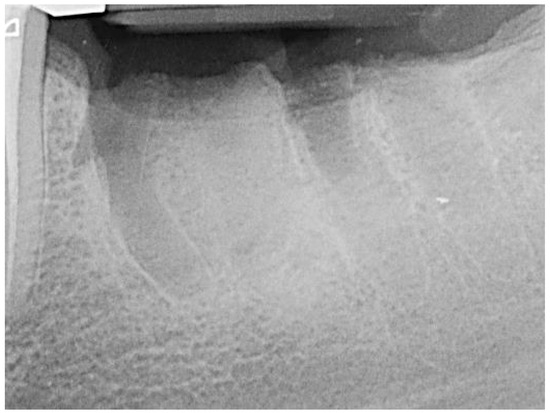

2. Materials and Methods